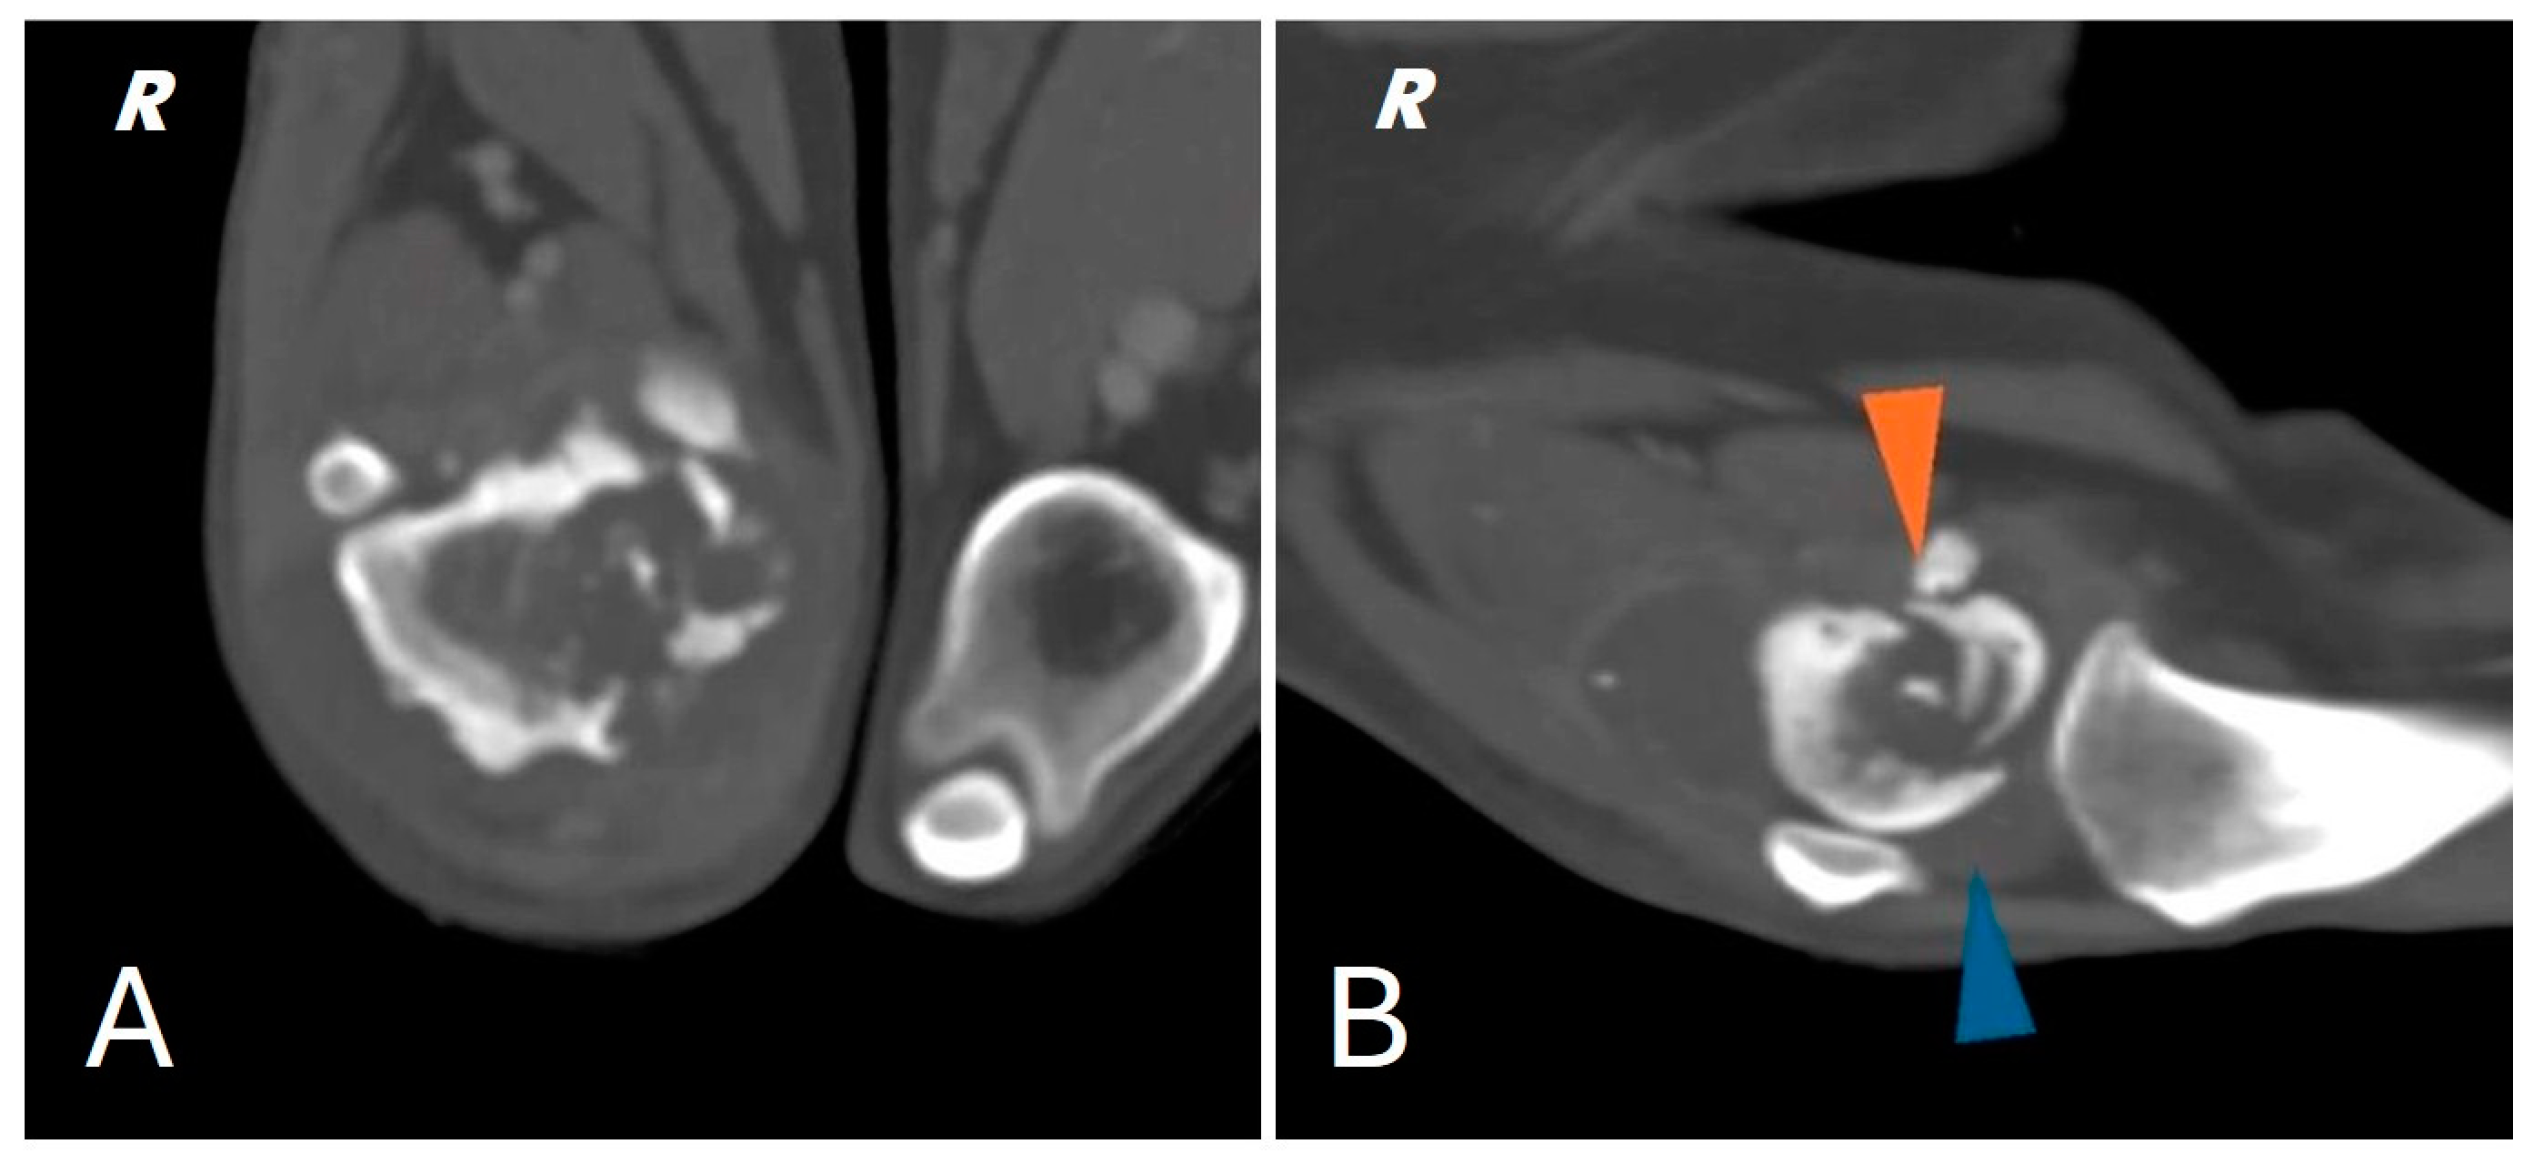

A total body computed tomography (CT) study using a 16-slice helical scanner (Somatom Emotion 16; Siemens, Erlangen, Germany) was performed to determine the extent of the neoplasm and its borders, the degree of cortical proliferation and soft tissue infiltration and the presence of any pulmonary metastases that were not visible on conventional radiography. The patient was sedated with a combination of intravenous dexmedetomidine (Dexdomitor, Vétoquinol Italia S.r.l., Bertinoro, Italy; 0.005 mg/kg) and butorphanol (Dolorex, MSD Animal Health S.r.l, Milan, Italy; 0.3 mg/kg) and then positioned in sternal recumbency with both thoracic limbs extended cranially and both pelvic limbs extended caudally. The CT acquisition parameters were 120 kVp and 150 mAs. A helical total body scan was reconstructed in a pre- and post-contrast 1 mm standard algorithm, and a 0.6 mm scan from the ilium to the toes was reconstructed using the bone algorithm. Contrast was administered IV at a dose of 770 mg iodine/kg of non-ionic contrast (Omnipaque, 350 mg iodine/mL, GE Healthcare Inc., Marlborough, MA, USA). After the acquisition of the planning CT study, the surgeon evaluated the tumor with a radiologist. The examination confirmed the presence of an aggressive lesion localized to the right distal femur, characterized by marked bone lysis, pronounced periosteal reaction and extensive increase in intramedullary density extending into the middle third of the diaphysis of the femur (Figure 2).

Figure 2.

(A) CT scan of the right distal femur. (B) CT scan of the knee joint; pathologic fracture of the medial femoral condyle (orange arrowhead) joint effusion (blue arrowhead).

In addition, CT showed a complete comminuted and slightly dislocated fracture of the medial femoral condyle ipsilateral to the injury, with marked swelling of the joint and periarticular soft tissues extending to the course of the long digital extensor, hypomyotrophy of the right limb with mild lymphadenomegaly of the medial iliac and sacral lymph nodes on the same side. Multifocal osteoarthrosis involving the elbow, tarsi and coxofemoral joints with mild bony remodeling, smooth margins and mild joint tumefaction were also noted. The CT scan showed no evidence of pulmonary metastases.